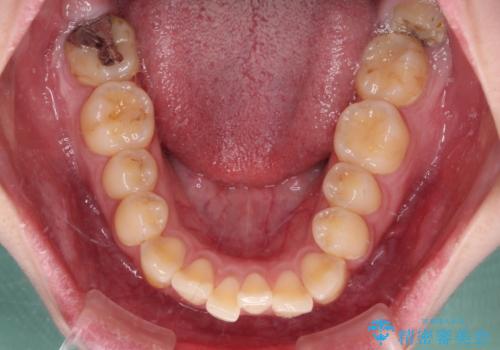

- 前歯のデコボコとクロスバイトが気になり、インビザラインによる矯正治療を希望して来院された患者様です。

上顎側切歯(上の真ん中から2番目の歯)が舌側転位している場合、無理して動かそうとすると歯髄壊死を起こすリスクが高い印象があります。

インビザライン単体でも治療は可能ですが、安全策としてインビザラインで歯列を移動する前に上顎前歯をワイヤー矯正で整え、その後上下歯列をインビザラインにて矯正治療を行うこととしました。

舌側転位している側切歯特有の、切縁の位置が不揃いであったり、根元が内側に引っ込んだ状態であったりという、インビザライン独特の仕上がりになることなく、きれいに整った歯列とすることができました。